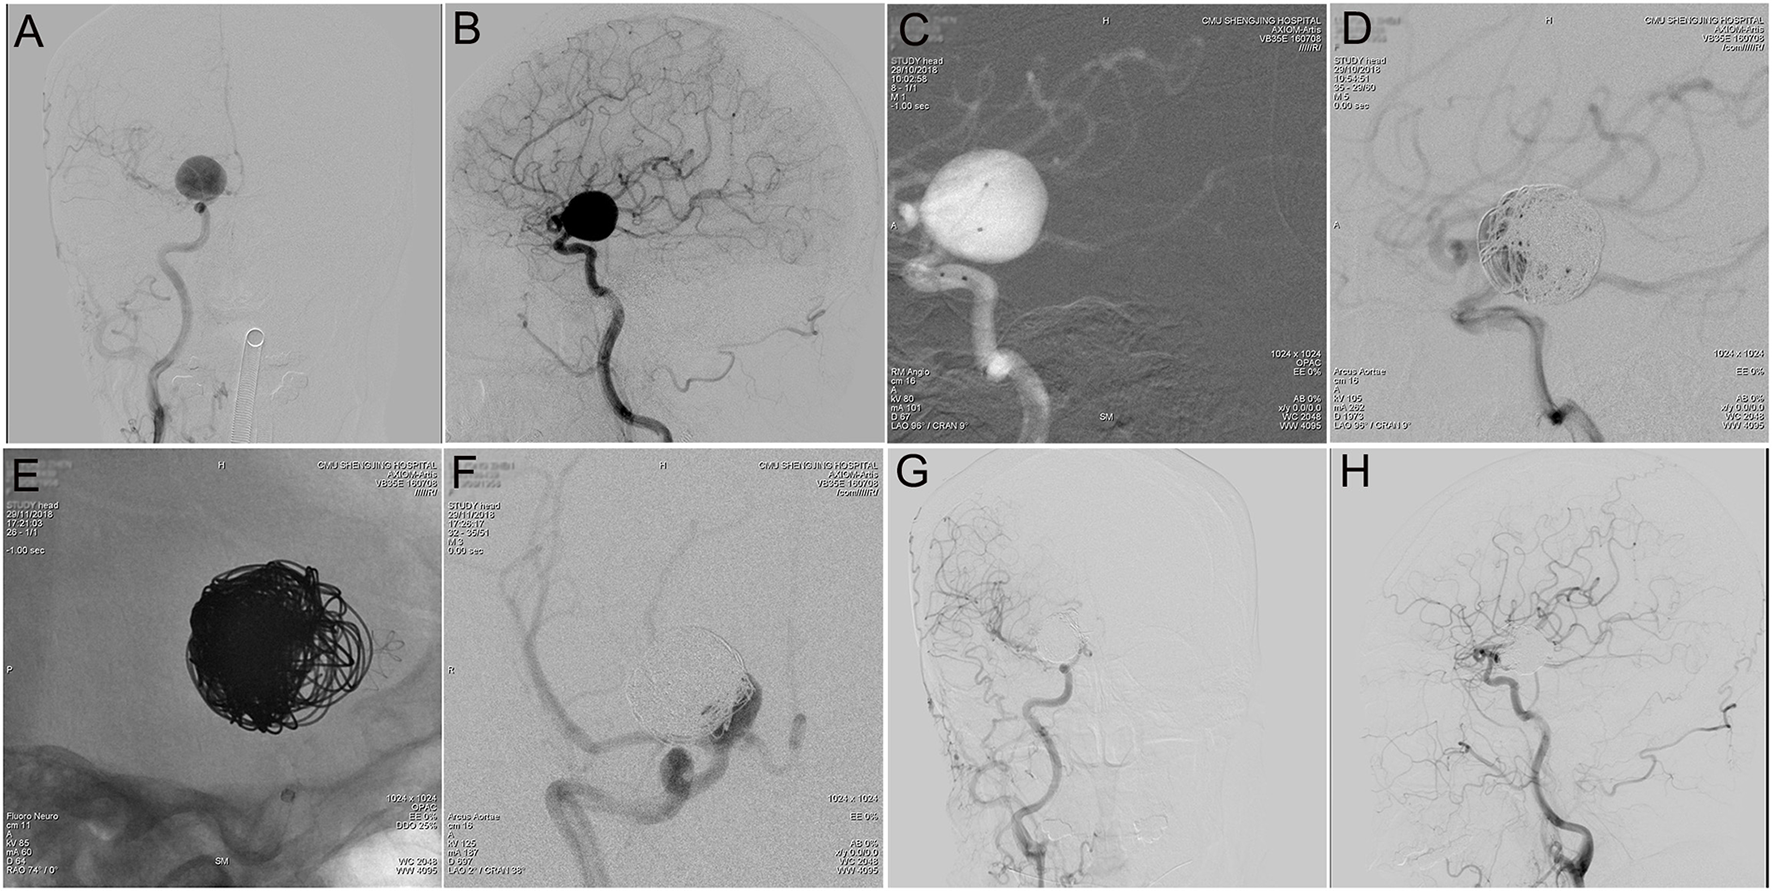

Figure 2

Tubridge™ treatment of a giant wide-necked aneurysm in the clinoid segment of the internal carotid artery. (A) DSA results shows a giant wide-necked aneurysm in the clinoid segment of the right internal carotid artery; (B) working angle measurement indicates an aneurysm size of approximately 21.4 mm × 20.5 mm and an aneurysm neck of 13 mm; (C) application of the double-microcatheter technique with spring ring embolization of the aneurysm to support the second-stage Tubridge™ release; (D) immediate postoperative imaging to complete most of the aneurysm embolization; (E) after 1 month, the second stage of Tubridge™ release is 3.0 × 25, and the stent is massaged by the microcatheter to make the stent fit the wall completely; (F) immediate DSA imaging shows a small amount of residual aneurysm neck; and (G,H) 2 years after surgery, DSA re-examination shows complete healing of the aneurysm.